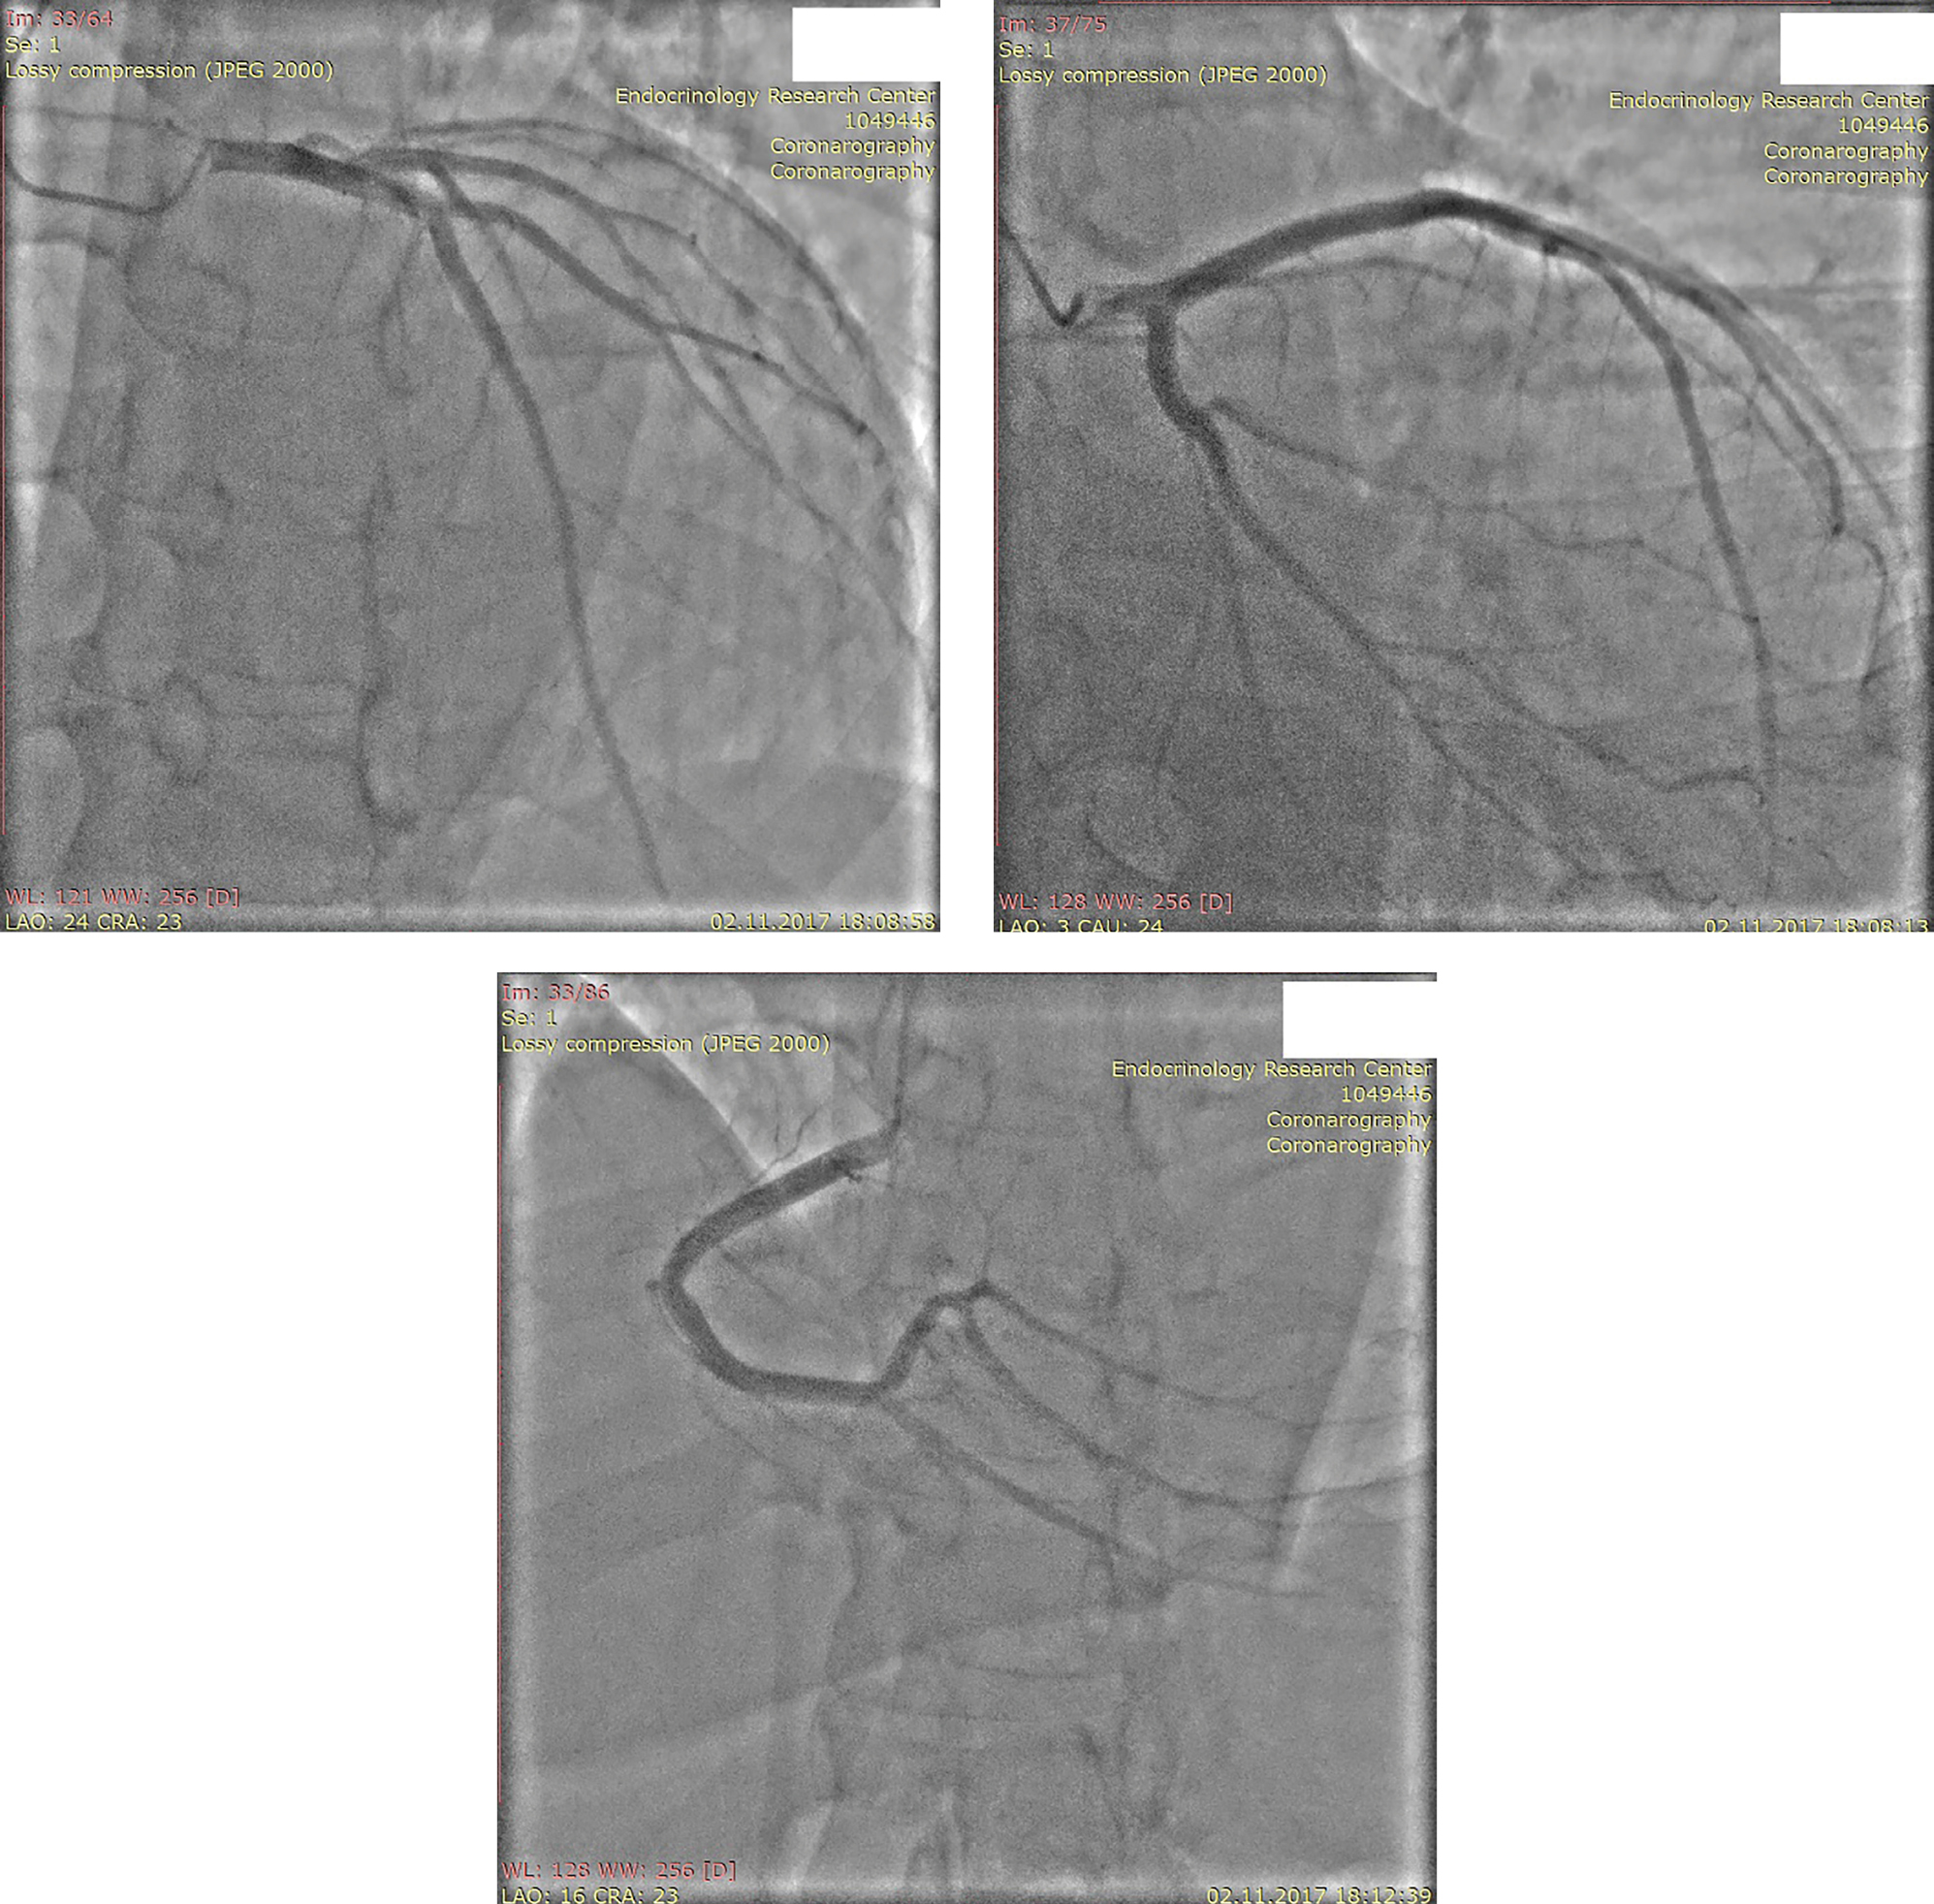

Пациент имел множественные факторы кардиоваскулярного риска (АГ, СД, атерогенная дислипидемия). С целью исключения ишемического генеза дисфункции ЛЖ была проведена коронароангиография (КАГ) (рис. 3). КАГ не выявила поражений коронарных артерий. Таким образом, было подтверждено предположение о неишемическом характере поражения миокарда.

Рисунок 3. Коронароангиография.

Примечание: сверху слева — ствол левой коронарной артерии, сверху справа — передняя межжелудочковая артерия, снизу — правая коронарная артерия.